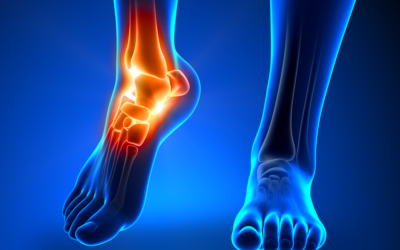

7 Serious Types of Foot and Ankle Injuries

There are numerous minor foot and ankle injuries that you can treat at home, usually with rest, an ice or heat pack, and some over-the-counter medications. However, some severe injuries require immediate medical attention to treat the injury, prevent it from getting...